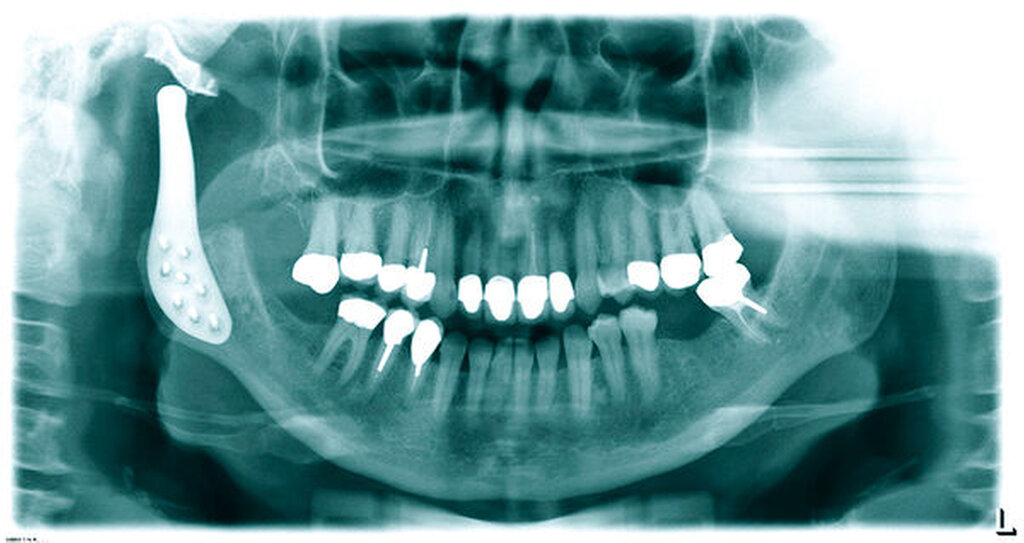

Im Jahr 2014 konsultierte uns die Patientin erneut und berichtete über eine progrediente Hypästhesie und Parästhesie des rechten N. alveolaris inferior. Die klinische Untersuchung zeigte eine harte und schmerzhafte Schwellung im Bereich rechten Kiefergelenks. Die Mundöffnung war auf 30 Millimeter reduziert. Die Orthopantomografie und der CT-Scan zeigten eine multizystische Auftreibung des rechten Ramus ascendens mandibulae sowie des rechten Capitulums mandibulae, die zu einer ausgeprägten Deformation führte (Abbildungen 1 und 2).

Basierend auf den klinischen und den radiologischen Merkmalen entschlossen wir uns mit der Patientin zur Resektion des rechten aufsteigenden Ramus, einschließlich des Processus coronoideus und des Kiefergelenks, sowie zur sofortigen totalen Kiefergelenkrekonstruktion mit einer CAD/CAM-gefertigten Prothese (Abbildung 3). Die Operation wurde nach Planung und Herstellung der Prothese über einen extraoralen Zugang unter Allgemeinanästhesie durchgeführt.

Das charakteristische röntgenologische Erscheinungsbild des Tumors wird als uni- oder multilokuläre radiologische Aufhellung beschrieben, die Seifenblasen oder Honigwaben ähnelt. Radiologisch kann sie sowohl gut abgrenzbar als auch unscharf begrenzt sein [Kawai et al., 1997; Peltola et al., 1994].

Die Darstellung einer multilokulären radioluzenten Läsion im rechten Ramus ascendens und Kondylus, einschließlich des Kiefergelenks mit starker Deformation und seifenblasenähnlicher Erscheinung mit klar definierten Rändern, passt zu den in der Literatur für das odontogene Myxom beschriebenen radiologischen Merkmalen [Kawai et al., 1997]. Die histopathologische Analyse des Präparats durch das Institut für Pathologie des Universitätsspitals Basel in der Schweiz (Prof. Dr. Jundt) zeigte stern- und spindelförmige Zellen innerhalb einer myxoiden Matrix, die als typische histologische Merkmale für das odontogene Myxom gelten.